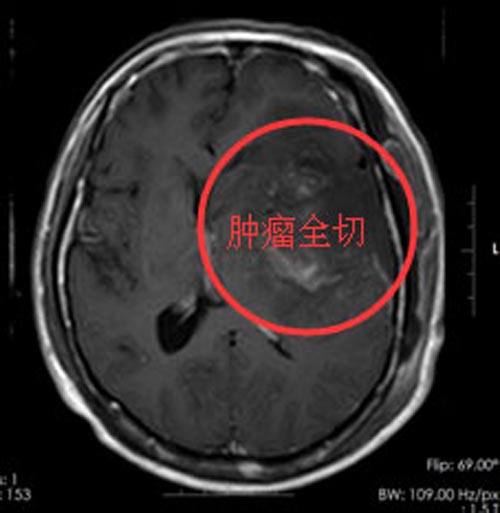

进一步检查发现:左额颞岛叶及基底节区块状占位性病变,病灶范围约7.2cm×4.7cm×5.4cm,左侧脑室受压变窄,中线结构稍右偏,周围脑组织水肿明显,有手术指征。家属同意手术治疗。

肿瘤位于功能区的语言中枢和运动中枢,与周围组织分界不清,既要最大限度地全切肿瘤,降低复发率,又要保护患者的语言及运动功能,这成为该手术的重中之重。由鲁明副院长主刀在全麻下行“左额颞岛叶及基底节区占位切除术”,术程顺利。术后,徐先生恢复满意,说话流利了许多,左侧肢体活动好,右侧肢体乏力也得到明显的改善。术后病理:非典型脑膜瘤,WHOⅡ级。